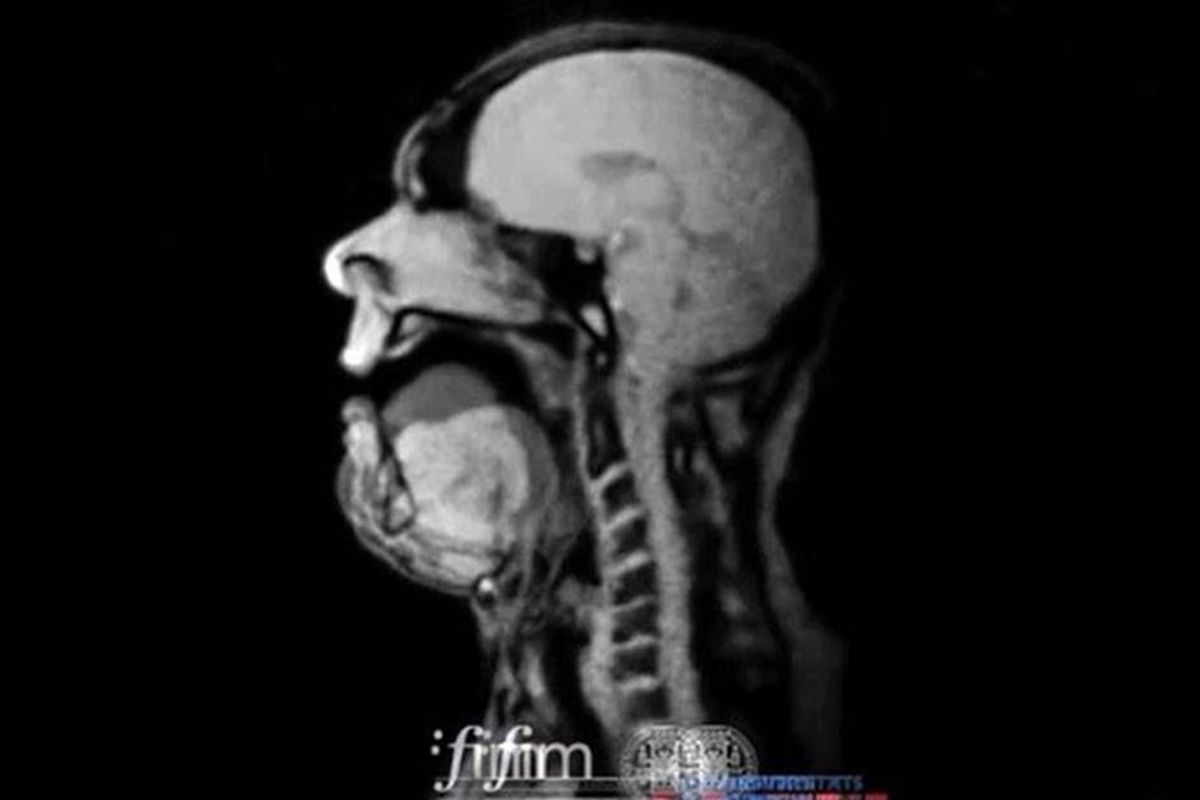

An MRI Of opera singer Michael Voll performing Wagner

MRI image of an opera singer, singing.

German baritone Michael Volle performed "Song to the Evening Star" by German composer Richard Wagner while inside of an MRI scan to give people a never-before-seen look at how an opera singer produces such a haunting sound. It's a pretty freaky-looking image, but shows the amazing control these performers must have to hit such powerful notes.